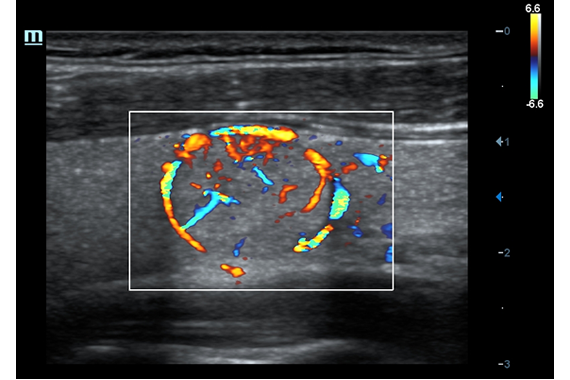

• Поддержка режимов сканирования B/M/Цветовой доплер CDI/Цветной M/Энергетический доплер PD/Направленный энергетический доплер Dir.PD.

• HR Flow - режим отображения кровотока с высоким временным и пространственным разрешением для точной и однородной визуализации сосудов, в том числе самых мелких.

Энергетический допплер:

Цветовой допплер:

• HR Flow - режим отображения кровотока с высоким временным и пространственным разрешением для точной и однородной визуализации сосудов, в том числе самых мелких